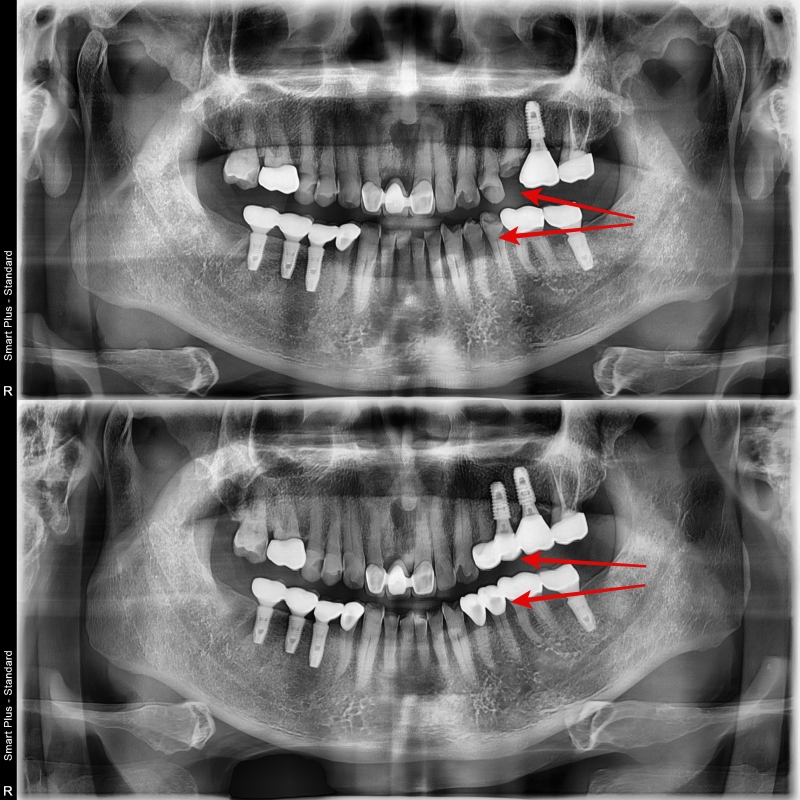

이런 이유들로 장기적으로 보았을 때 제대로 된 교합을 형성해 주기 위해 주변 치아들의 보철 치료가 필요했고, 환자분께 상기 이유에 대해 자세히 설명드렸고, 환자분께서는 치료에 대한 필요성에 대해 이해하시고 보철치료를 같이 진행하게 되었습니다.

치료 후 엑스레이 사진입니다

하얀색으로 보이는 부분이 보철물로 인해 회복된 치아입니다.

신경치료 없이 치아의 생활력을 유지한 채 치료는 마무리되었습니다.

정기적으로 검사를 하며 지내시면 기존 파절 상태보다 치아의 수명은 늘어날 것입니다.

기존 치아들은 지르코니아 보철물로 회복이 되었고, 보험 임플란트는 교합면의 힘을 지지해 줄 수 있는 메탈 교합면을 선택했습니다.

마모된 치아의 외형을 복원함으로써 위아래 어금니의 균형 잡힌 교합을 완성 시켜줄 수 있어 4개의 어금니에 균일한 교합력을 부여하였습니다.